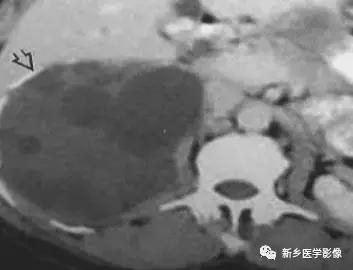

棘球蚴病